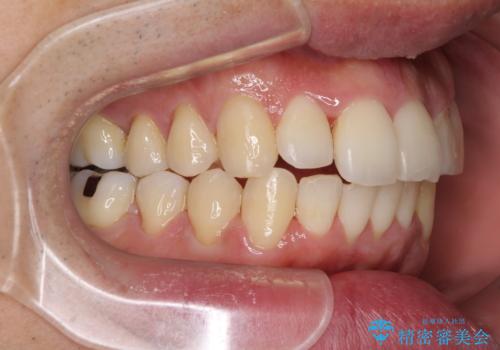

下顎骨が顕著な左右差を持って成長したため、右側にずれている状態でした。

この方は元々骨格的な偏位が大きかったためか、治療中に下顎骨が上顎骨よりも右外側に誘導されて、右側の奥歯が全く咬合しない状態が続いてしまいました。

最終的にはゴムかけなどを活用して改善することができましたが、4年近い治療期間を要することとなりました。